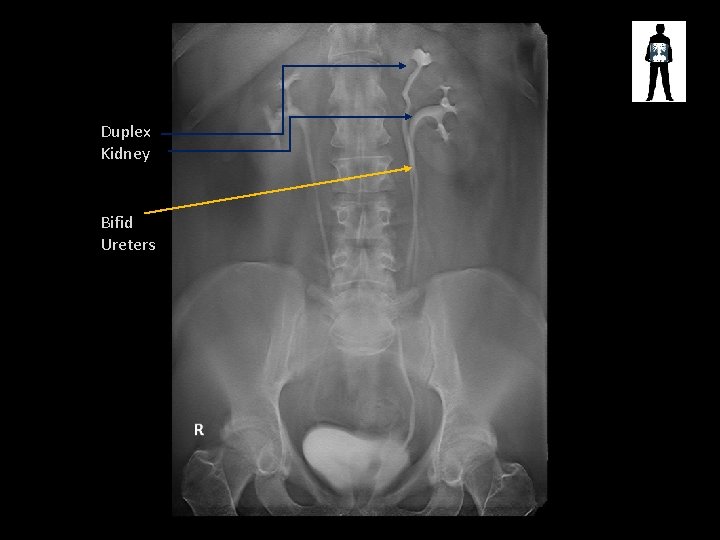

Duplex Kidney Bifid Ureters

STONES! • Cause pain and obstruction of renal/biliary systems – Can be treated by surgical removal or laser fragmentation, lithotripsy or if small enough just monitored until they pass • Patients may undergo fluoroscopic procedures to treat these stones – ERCP – Retrograde Ureterogram – etc